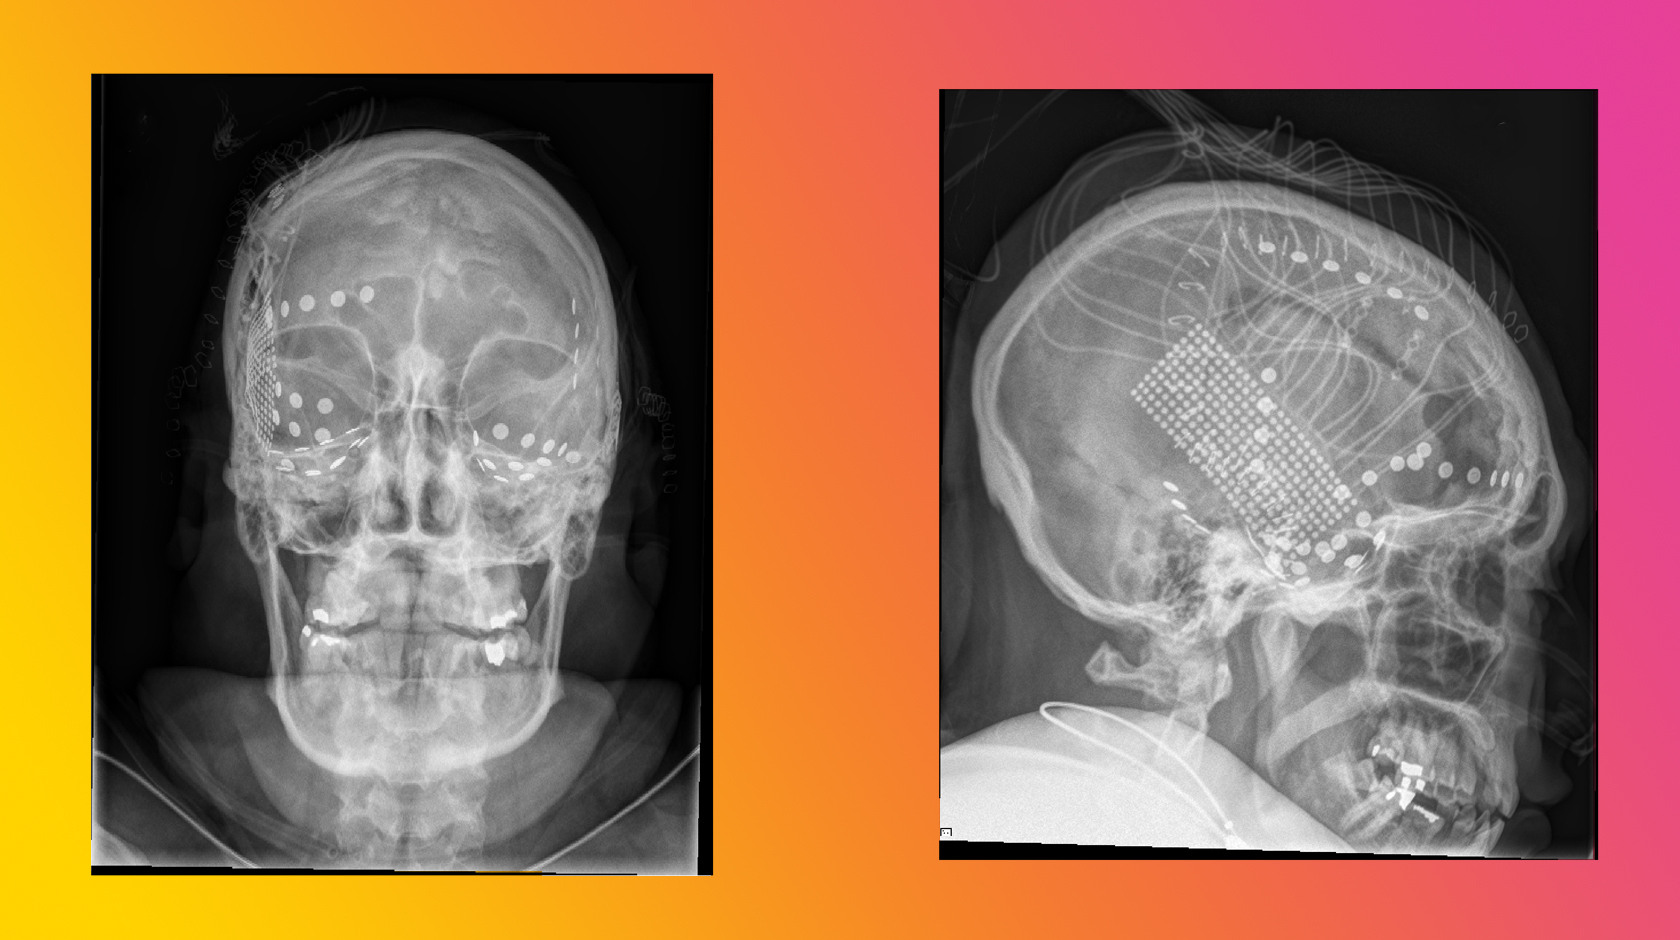

A head X-ray of one participant in the experiment shows the placement of electrodes over the frontal (top) and temporal (bottom) regions of the brain. These electrodes were placed on the surface of the brain to locate the origin points of epileptic seizures. While waiting for days in their hospital rooms, patients volunteered for other brain studies, including one attempting to pinpoint the brain regions that respond to music.